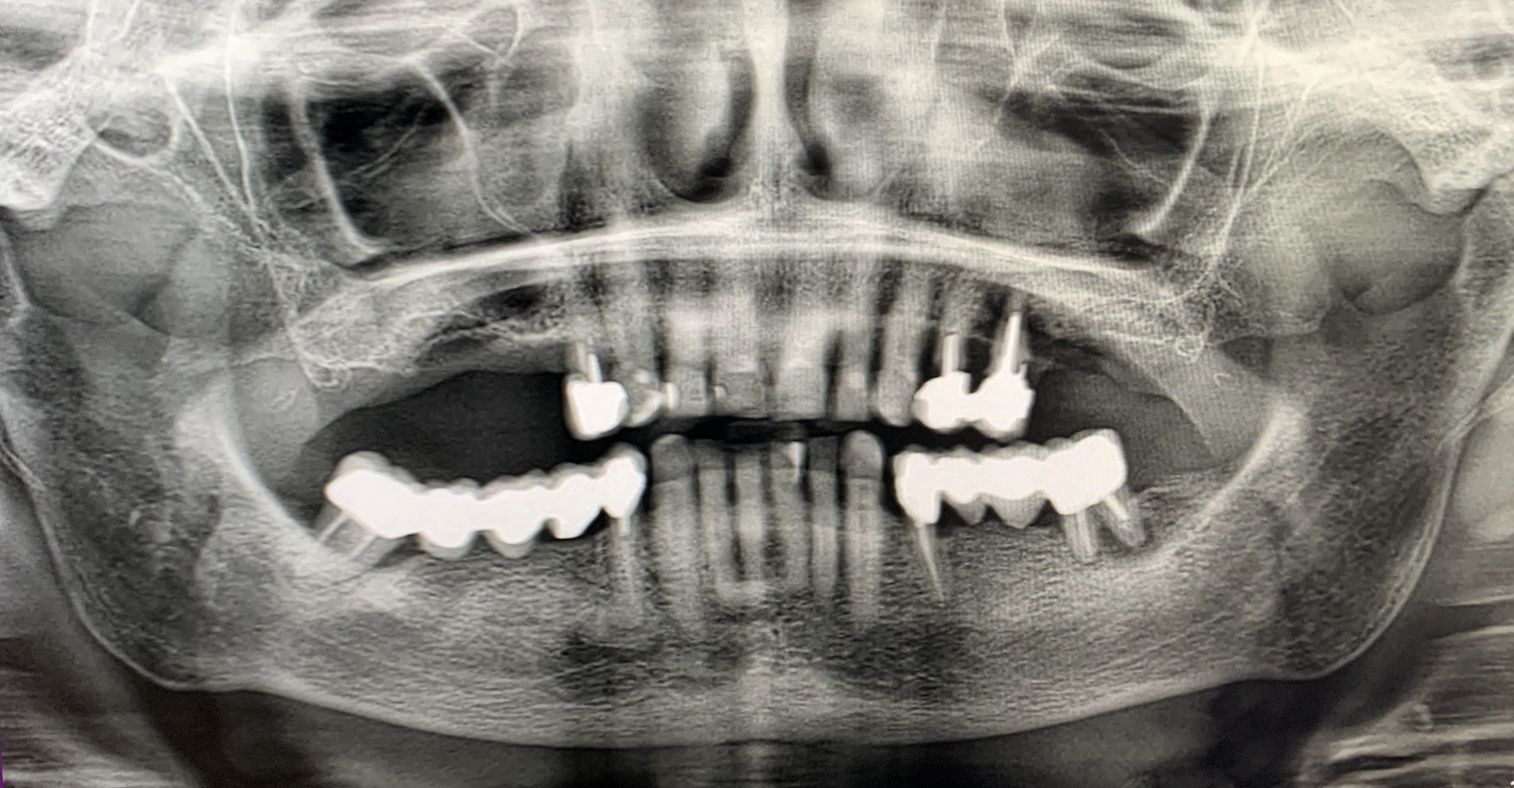

L'intervento chirurgico è stato eseguito in anestesia locali. Dopo il sollevamento di un lembo musopeiosteo a tutto spessore per esporre il mascellare, nei settori anteriori si è proceduto con la preparazione dei siti implantari secondo protocollo convenzionale. Gli impianti IS+ sono stati quindi posizionati (Fig. 2), ottenendo una buona stabilità primaria grazie alla presenza di un adeguato volume di osso residuo.

Fig. 2 - Impianti IS+

Nei settori posteriori, caratterizzati da significativa atrofia ossea e da pneumatizzazione del seno mascellare, è stato adottato un approccio transinusale. È stata pertanto realizzata una finestra laterale per consentire il sollevamento della membrana di Schneider (Fig. 3), procedura eseguita con particolare attenzione per preservarne l’integrità. Successivamente i siti implantari sono stati preparati con una traiettoria inclinata che attraversa la cavità sinusale, permettendo l'ancoraggio nell'osso basale anteriore. Sono stati quindi inseriti due impianti BT-Rhyno (Fig. 4), progettati specificatamente per l'inserimento transinusale e in grado di garantire adeguata stabilità anche in presenza di ridotto spessore osseo crestale.